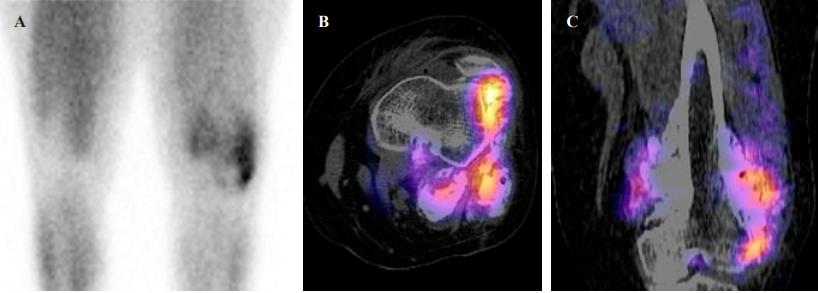

核医学:99mTc-MIBI成像报告骨病变,延伸至邻近软组织,放射性药物异常增加。病变向外侧摄取较多区域SPECT/CT报告外生性骨病变,位于干骺端,具有异质外观,放射性药物异常增加。病变呈多发阳性灶区(图4)。

图4、(A)软组织放射性药物异常增高。病变向外侧区域摄取较多。SPECT/CT轴位(B)和矢状位(C)。放射性药物异常增高的多发病灶区